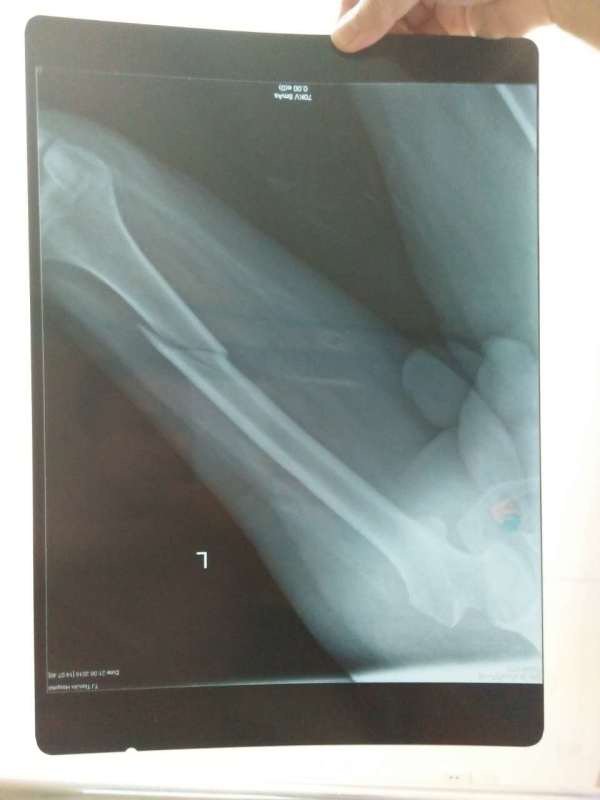

父亲大腿骨折~因为左侧腿有小儿麻痹,无法做手术~一直做的牵引,现出院在家做牵引~父亲大腿骨折~因为左侧腿有小儿麻痹,无法做手术~一直做的牵引,现出院在家做牵引~下面还需要继续牵引吗?还需要后续什么措施吗?片子附上~请大家帮我看一下~非常感谢

对位对线不良,还是要继续牵引直到长愿蛋出潜耻骨痂长结实为止。 有些主要下肢肌肉肌力正常的小儿麻痹症患者,手术还编印最是可进行的。